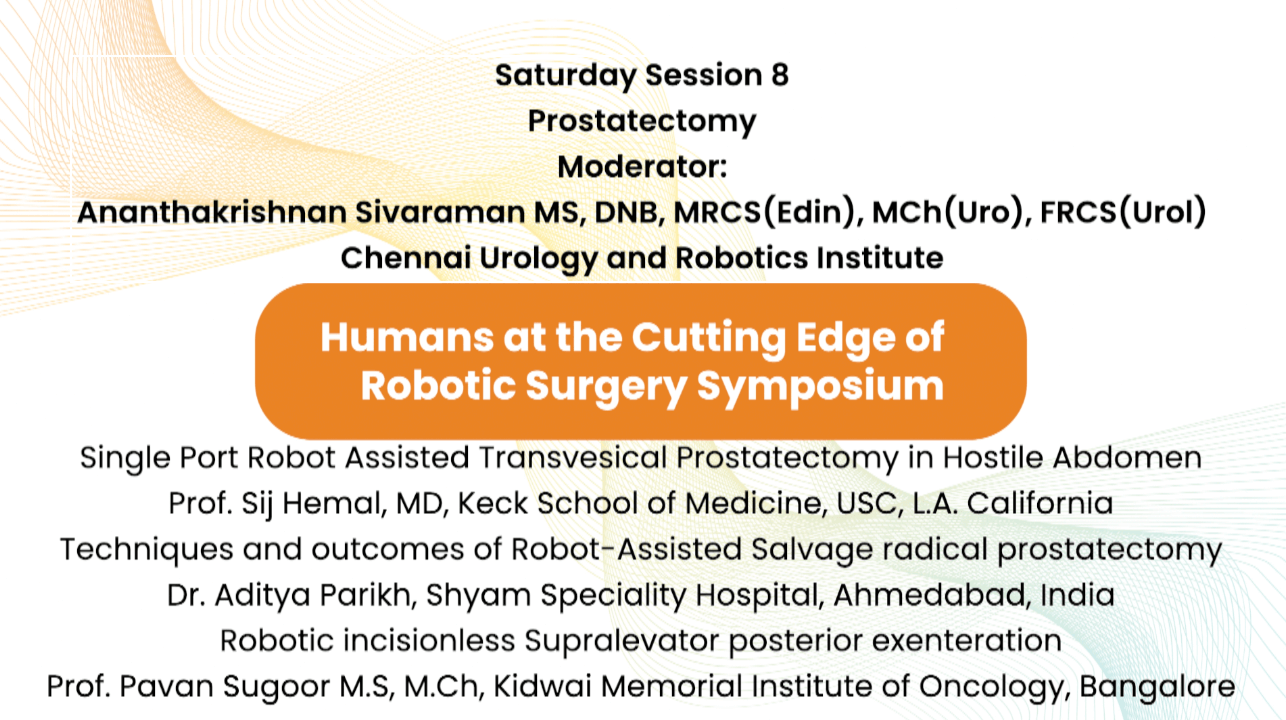

Jaipur Saturday Session 8 Prostatectomy

Humans of Robotic Surgery, KS Awards, Robotics, Surgeon, Video Library ';